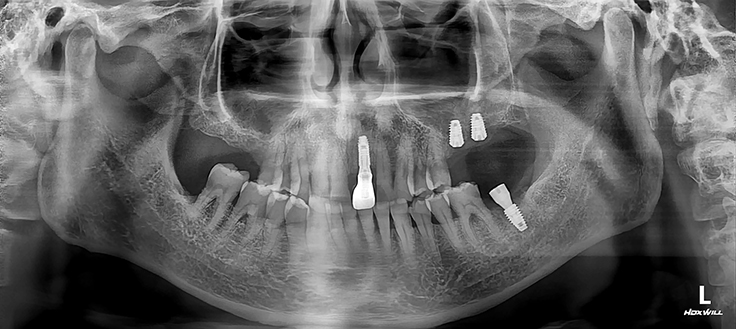

위 사진에 보이는 화살표로 표시된 치아중에 어떤게 임플란트 치아일까요?

참고로 임플란트 치료한지 5년이 경과된 상태입니다.^^

오른쪽 치아입니다.(환자분 입장에서는 왼쪽)

위의 사진이 치료 후, 아래 사진이 치료 전 사진인데 확연한 차이가 느껴지시나요?

치료전에는 겨우 겨우 남아있는 치조골에 비해 치료 후의 사진을 보시면

충분하게 잘 만들어진 치조골이 임플란트를 안정적으로 고정하고 있지요.